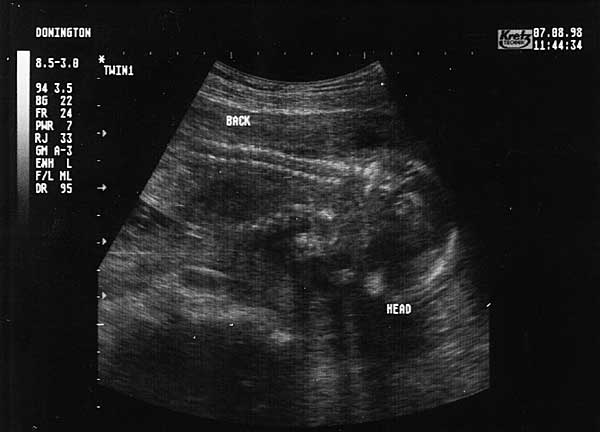

19 Weeks - Friday 7th August 1998.

Nineteen Week Scan 2